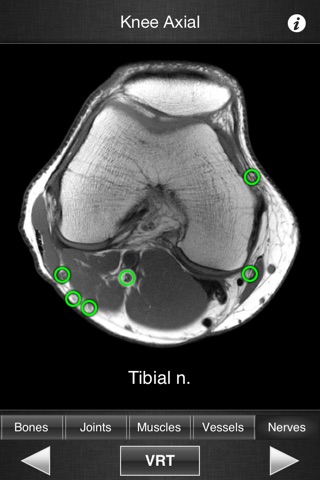

This application is designed for healthcare professionals (Radiologists, General Practitioners, Orthopedists, Surgeons, Physiotherapists among others) as well for students, as a reference and learning tool. It contains 82 contiguous knee MR slices (4-5 mm thickness) in the three anatomical planes.

- The five different display modes available (bones, joints, muscles, blood vessels and nerves) facilitates label visualization.